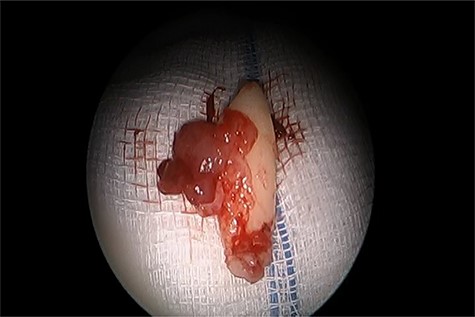

An 11-years-old girl known case of acute lymphocytic leukemia on remission, presented to otolaryngology clinic with right-sided nasal obstruction along with occasional headache. Symptoms are progressive over a period of 1 year. No history of trauma, surgery or foreign body. Examination showed a collapsed right lower lateral cartilage, supratip depression and hard bony mass filling the right nasal cavity. No other remarkable findings. CT of the paranasal sinuses is done and it shows displaced right upper maxillary tooth with crown oriented inferiorly and medially toward and within the lower right anterior nasal cavity with no destruction of the adjacent structures (Fig. 4A and B). Patient was managed with anterior rhinoscopy and endoscopic-guided removal of the ectopic tooth without any complications. The ectopic tooth is found to be canine tooth (Fig. 4). Histopathologic report confirms the diagnosis of ectopic tooth. Post operatively, the patient symptoms improved completely, and she remained symptoms free for 18 months.